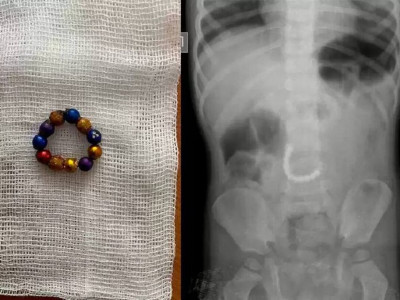

Дәрігерлер магнит жұтып қойған баланы аман алып қалды